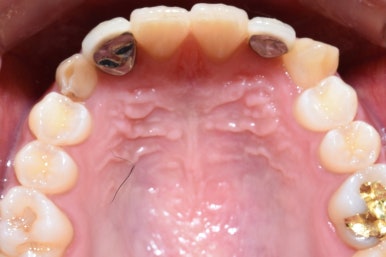

전후를 비교하면 위와 같습니다.

정면과 교합면 사진입니다.

고르고 깔끔하면서 길쭉길쭉 시원해 보이는 이로 바뀌었습니다.

오른쪽 교합면 전후를 비교해 보면 확실히 더 고르게 된 것을 볼 수 있으며

환자분이 싫어했던 쑥 안으로 들어가 있던 옥니? 옹니? 도 앞으로 나오게 개선되어서

훨씬 더 예쁜 미소를 가질 수 있게 되었습니다.